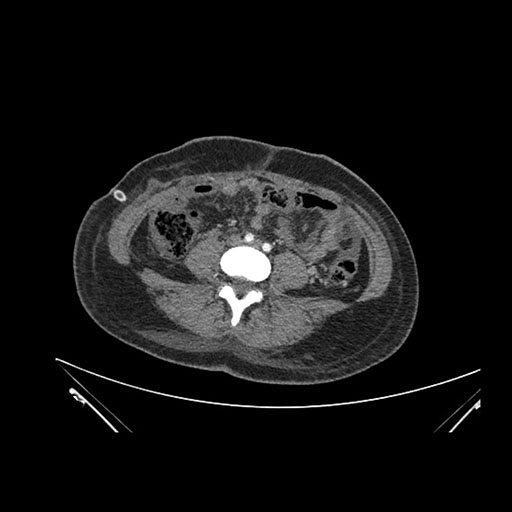

Imaging Analysis

Look through the patient's CT scan to identify any areas of concern for the necessary procedure.

Coronal Venous